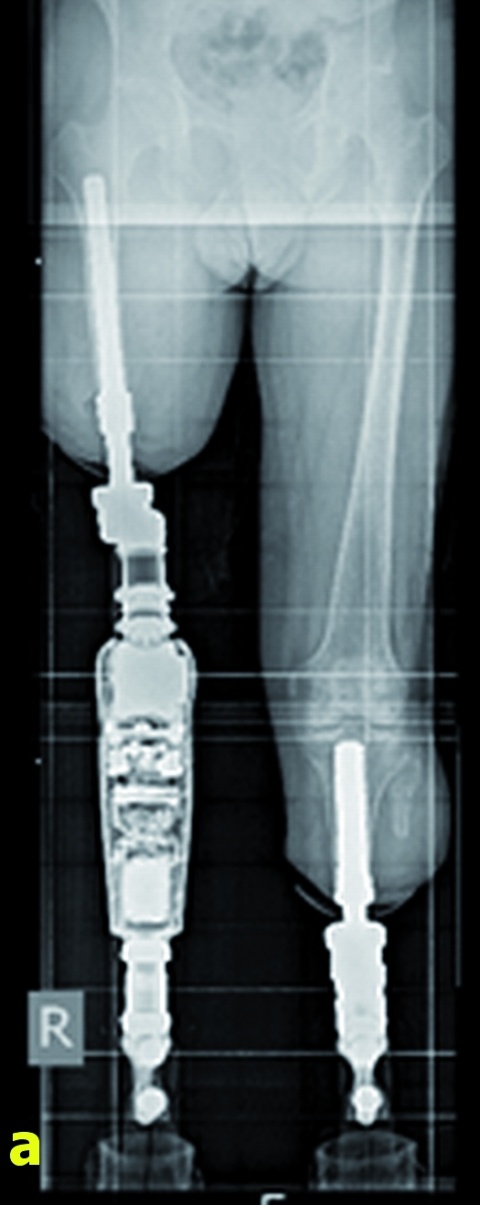

Ende April 2016 kehrte der Patient in seine Heimat zurück; die Wiederaufnahme zur Durchführung des zweiten Operationsschrittes war für Mitte Juli 2016 geplant. Hier erfolgte planmäßig die „St

omatisierung“ beider Stümpfe. Zur Ausbildung des „Stoma“ wird eine Perforation in der Haut über dem Knochen geschaffen, so dass später die anzudockenden externen Prothesenteile (Exo-Anteil) mit den internen, in den Schaft implantierten und in den Knochen fest integrierten Metallimplantaten (Endo-Anteil) zur Bildung der Endo-Exo-Prothese verbunden werden können.

Zwei Tage nach Anlage der Stomata wurden dann durch den Orthopädietechniker die Exoprothesen achsengerecht montiert, so dass der Patient noch am gleichen Tag erstmalig seit dem Unfallgeschehen wieder direkten Bodenkontakt über die im Knochen verankerten Implantate verspürte. Das weitere Gehtraining begann eine Woche später in einer benachbarten Rehabilitationsklinik. Der Patient ist zur Zeit (8. November 2016) mit seinen neuen beidseitigen integralen Prothesen beschwerdefrei unter Vollbelastung mobilisiert, die Weichteilverhältnisse im Bereich der Hautdurchtrittsstelle sind reizfrei (Abbildung 6b). Eine Wiedervorstellung zur Kontrolluntersuchung ist für Februar 2017 geplant.